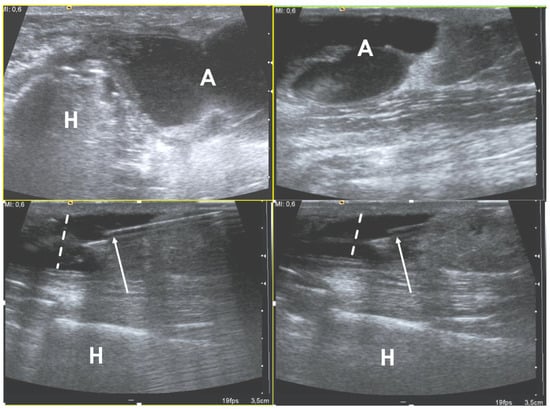

2.2. Necrotizing and Non-Necrotizing Fascitiis

| US | • Increased echogenicity and thickening of subcutaneous soft tissue • Fluid tracking along the fascia • Gas seen as echogenic foci with dirty posterior acoustic shadowing |

| MRI | • Thickening of deep fascia ≥ 3 mm • Fluid extending deep along intermuscular fascial planes • Involvement of more than 3 compartments • Variable enhancement with areas of fascial enhancement (inflammation) and lack thereof (necrosis) • Gas seen as foci of signal void on all sequences • May be band like edema/enhancement in periphery of muscles |